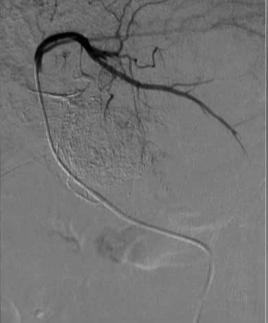

血管造影发现腹腔干狭窄,通过肠系膜上动脉侧支建立通路(图二)。

微导管精准置入肝动脉,缓慢输注顺铂(75mg/m²)及吉西他滨(1000mg/m²),联合DSM微球栓塞(图三)。

结果:术后8个月肿瘤显著缩小,未出现严重并发症。